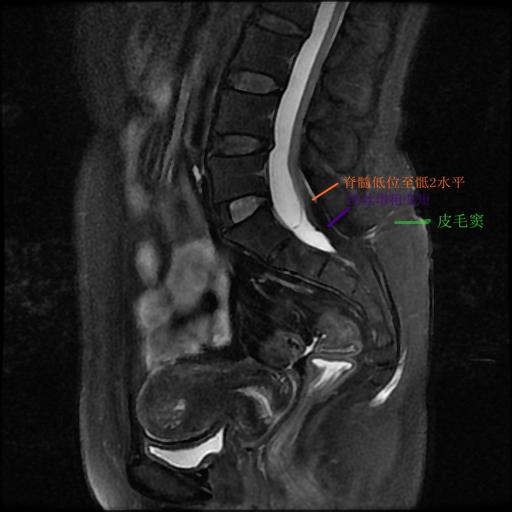

刘女士近年长期受到腰腿疼痛、行走困难、便秘困扰,严重影响正常生活。辗转多家医院就诊治疗,打针、吃药、康复理疗等方法都试过后仍收效甚微,成了名副其实的疑难杂症。饱受病痛折磨的刘女士感到人生晦暗,心存不甘的她慕名来到我院就诊。神经外科脊髓脊柱亚专科团队专家们缜密分析病情发现,刘女士除上述症状外,腰骶部有皮毛窦,同时合并有马蹄足,腰骶椎磁共振显示脊髓低位。她所患诸多症状的病根是脊髓拴系综合征,脊髓发育过程中出现异常,使脊髓、马尾神经和终丝受到牵拉,造成腰退疼痛、双下肢和二便功能障碍。旷日持久,可能导致瘫痪及大小便*禁失**,需尽快实施手术治疗。

术前可见骶尾部皮毛窦

术前MRI见低位圆锥,终丝短粗